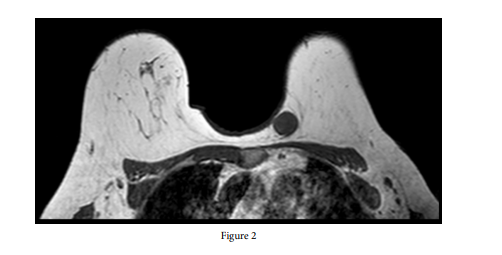

On magnetic resonance imaging, an 18x23-mm lesion was detected in the left breast, which was hypointense in the T1-weighted series (Figure 2) and hyperintense in the T2-weighted series (Figure 3). In the dynamic examination, there was a round lesion with smooth borders and intense heterogeneous contrast enhancement from the early period onwards (BI-RADS category 4a findings). In the second core biopsy, upon reviewing the histopathological findings and immunohistochemical and histochemical staining pattern together, it was considered that there might be a neoplasia of neural origin, but the total excision of the described lesion was recommended for a definitive/differential diagnosis. The mass was completely excised. In the detailed pathological examination, a nodular, smooth-surfaced, homogeneous mass lesion with a widest diameter of 2 cm was observed macroscopically in the sections of the sample. The microscopic examination of the lesion revealed a mesenchymal tumor consisting of spindle-ovoid cells containing mixed hypocellular and hypercellular areas, without apparent atypia or mitotic activity. Ancient changes, including myxoid change, hyalinization, old hemorrhage, and enlargement of the nuclei, were noted in the tumor. Immunohistochemically, S100 was diffusely strong, and CD34 was focally weakly positive in the cells. Desmin and actin were negative. The Ki-67 proliferation index was around 1-2%. The diagnosis of breast schwannoma was confirmed by histopathological examination (Figure 4).